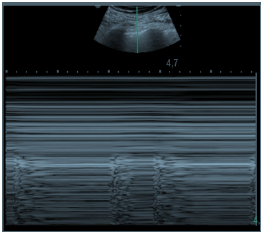

Um paciente de 50 anos de idade encontra-se, internado na UTI por conta de choque séptico de foco pulmonar, em ventilação mecânica na modalidade pressão e no modo assisto-controlado. Pela manhã foi submetido a acesso venoso central em veia axilar guiado por ultrassonografia. Ao exame físico, notou-se que o paciente está com hipotensão e taquicardia. A primeira hipótese diagnóstica é pneumotórax e é realizada radiografia com imagem apresentada.

Qual imagem abaixo corresponde ao achado ultrassonográfico para o paciente em questão?